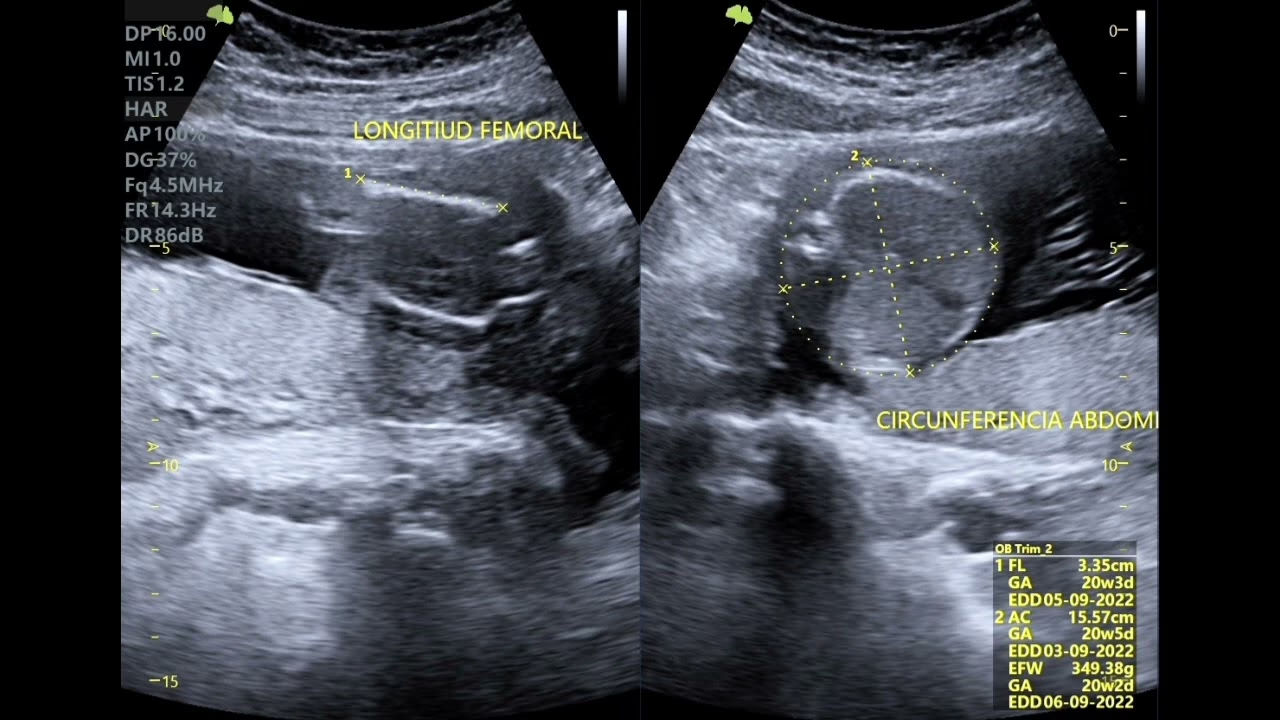

Durante las ecografías rutinarias del embarazo, especialmente en el segundo y tercer trimestre, se utilizan varios parámetros biométricos para evaluar el crecimiento fetal. Estos se comparan con tablas de referencia estandarizadas que permiten determinar si el bebé está creciendo dentro de los rangos esperados para su edad gestacional. Los parámetros más comúnmente medidos incluyen:

- Circunferencia del Abdomen (CA): Refleja el tamaño del abdomen fetal y es un indicador clave del crecimiento y la nutrición, ya que está influenciada por el tamaño del hígado.

- Longitud del Fémur (LF): Es la medición del hueso más largo del cuerpo del bebé, el fémur. Esta medida es muy fiable para estimar la longitud del cuerpo y la edad gestacional, especialmente en etapas avanzadas.

La longitud del fémur es un indicador particularmente útil y robusto para estimar el tamaño total del feto. Aunque no se puede medir al bebé de pies a cabeza con una cinta métrica dentro del útero, la longitud del fémur proporciona una excelente aproximación. Los especialistas utilizan fórmulas específicas para convertir la medida del fémur en una estimación de la longitud total del bebé. Una de las fórmulas más utilizadas para este propósito implica multiplicar la longitud del fémur por siete (LF x 7).

Es importante recordar que esta medición, junto con la circunferencia de la cabeza, el diámetro biparietal y la circunferencia abdominal, contribuye a una estimación del tamaño total del bebé. Estas mediciones son aproximadas y pueden variar ligeramente. Factores como la posición activa del bebé durante la ecografía pueden dificultar la toma de medidas exactas, lo que puede llevar a pequeñas variaciones. Además, cada bebé es único; su crecimiento está influenciado por la genética de sus padres y la familia, lo que significa que no todos los bebés crecerán al mismo ritmo o alcanzarán las mismas medidas en las mismas semanas.

Estimación del Peso Fetal Mediante Ecografía

Además de estimar el tamaño, la ecografía también permite hacer una aproximación del peso del feto. Para ello, se emplean diversas fórmulas que combinan las mediciones del diámetro biparietal (DBP), la circunferencia del abdomen (CA) y, por supuesto, la longitud del fémur (LF). Si bien estas fórmulas son herramientas valiosas, es crucial entender que el peso fetal estimado tiene un margen de error considerable, que puede oscilar entre el 15 y el 20 por ciento. Esto se debe a la complejidad de medir un objeto en movimiento dentro de un entorno fluido y a las variaciones individuales del crecimiento.

La longitud del fémur (LF) es un parámetro clave en la ecografía para estimar el tamaño de tu bebé. Aunque no se puede medir la longitud completa del feto directamente con una cinta métrica en el útero, los médicos utilizan fórmulas. Una de las más comunes es multiplicar la longitud del fémur por siete (LF x 7). Esta cifra, combinada con otras medidas como el diámetro biparietal, la circunferencia de la cabeza y la circunferencia abdominal, proporciona una estimación global del tamaño de tu bebé. Por ejemplo, en la semana 23, el bebé puede medir entre 28 y 30 cm de la parte superior del cráneo a los talones, y pesar alrededor de 450 gramos, aunque estas son solo aproximaciones que varían entre individuos.

¿Qué parámetros se utilizan en la estimación del tamaño fetal durante la ecografía del tercer trimestre?

En el tercer trimestre, se utilizan los mismos parámetros de medición que en la ecografía de la semana 20. De rutina, se miden el diámetro biparietal (DBP), la circunferencia del abdomen (CA) y la longitud del fémur (LF). En casos específicos, pueden ser necesarias otras mediciones como el perímetro cefálico, la longitud del húmero, cúbito, radio, tibia o peroné, y el diámetro transcerebeloso. Estas mediciones se comparan con valores de referencia en tablas estandarizadas para conocer los percentiles fetales (P10, P50, P90) y evaluar si el feto está creciendo adecuadamente.